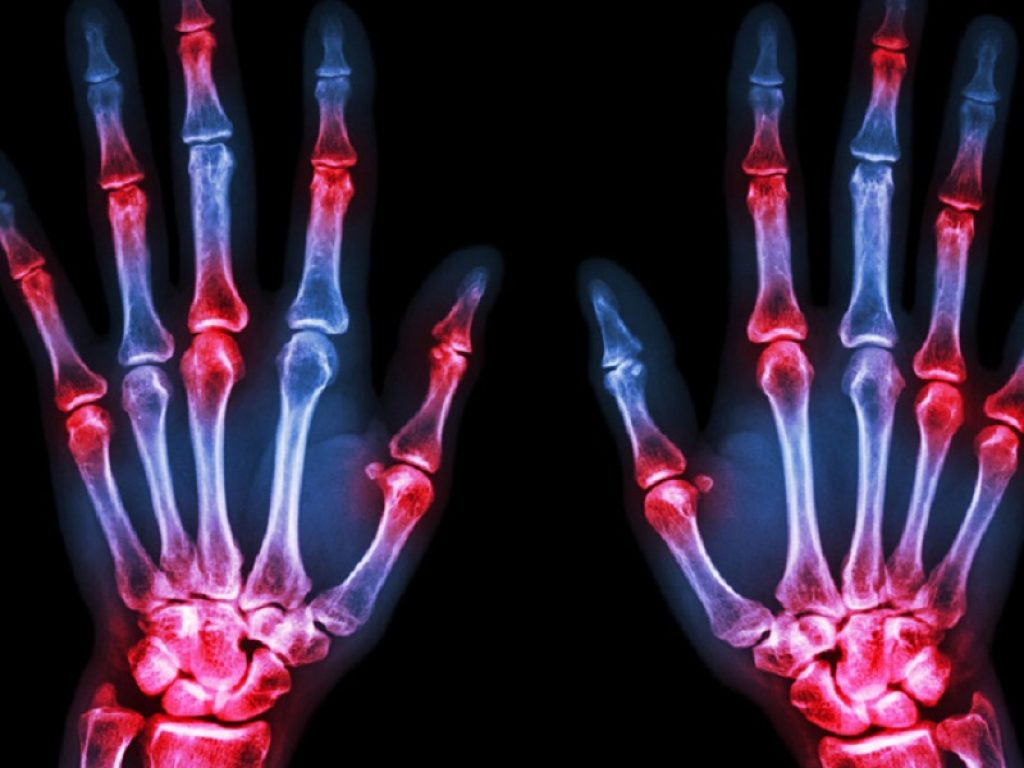

Un nuovo studio ha scoperto un’associazione tra la calprotectina e i punteggi ecografici di sinovite in pazienti con artrite reumatoide

Uno studio presentato nel corso del congresso ACR ha documento l’esistenza di un’associazione tra la calprotectina e i punteggi ecografici di sinovite in pazienti con artrite reumatoide (AR) trattati con inibitori di IL-6 e Jak inibitori, suggerendone la possibilità d’impiego come marker di sinovite attiva in questi pazienti.